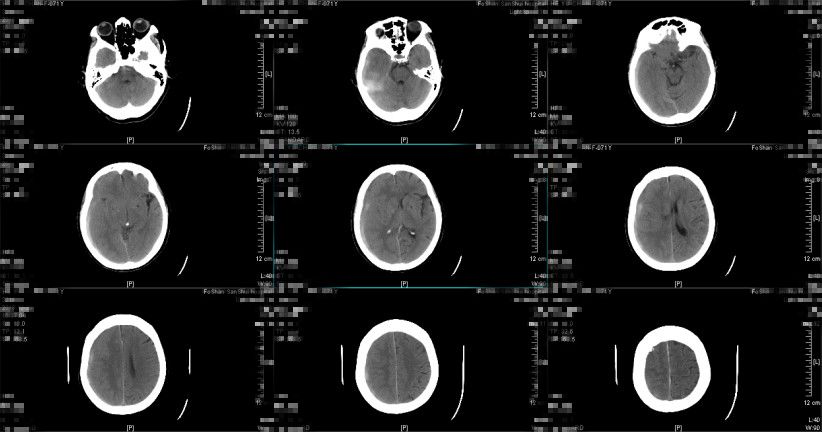

留置头部微创针引流管引流1天,引流量约200ml,患者神志清,头痛等症状减轻,复查头颅CT提示亚急性硬膜下血肿大部分消除,最大厚度约0.2cm,中线大致居中,环池清晰,手术效果明显,予拔除微创针引流管,继续与立普妥药物治疗。

图9. 术后24小时复查头颅CT提示:亚急性硬膜下血肿大部分消除,中线大致居中,环池清晰。(2019-01-04 10:01:05)

图10. 术后9天复查头颅CT提示亚急性硬膜下血肿基本吸收。(2019-01-12 16:17:43)

经治疗后,患者神志清,头痛等症状缓解,无遗留神经系统缺损体征,复查头颅CT提示亚急性硬膜下血肿基本吸收,病情稳定,于2019年1月14日出院。